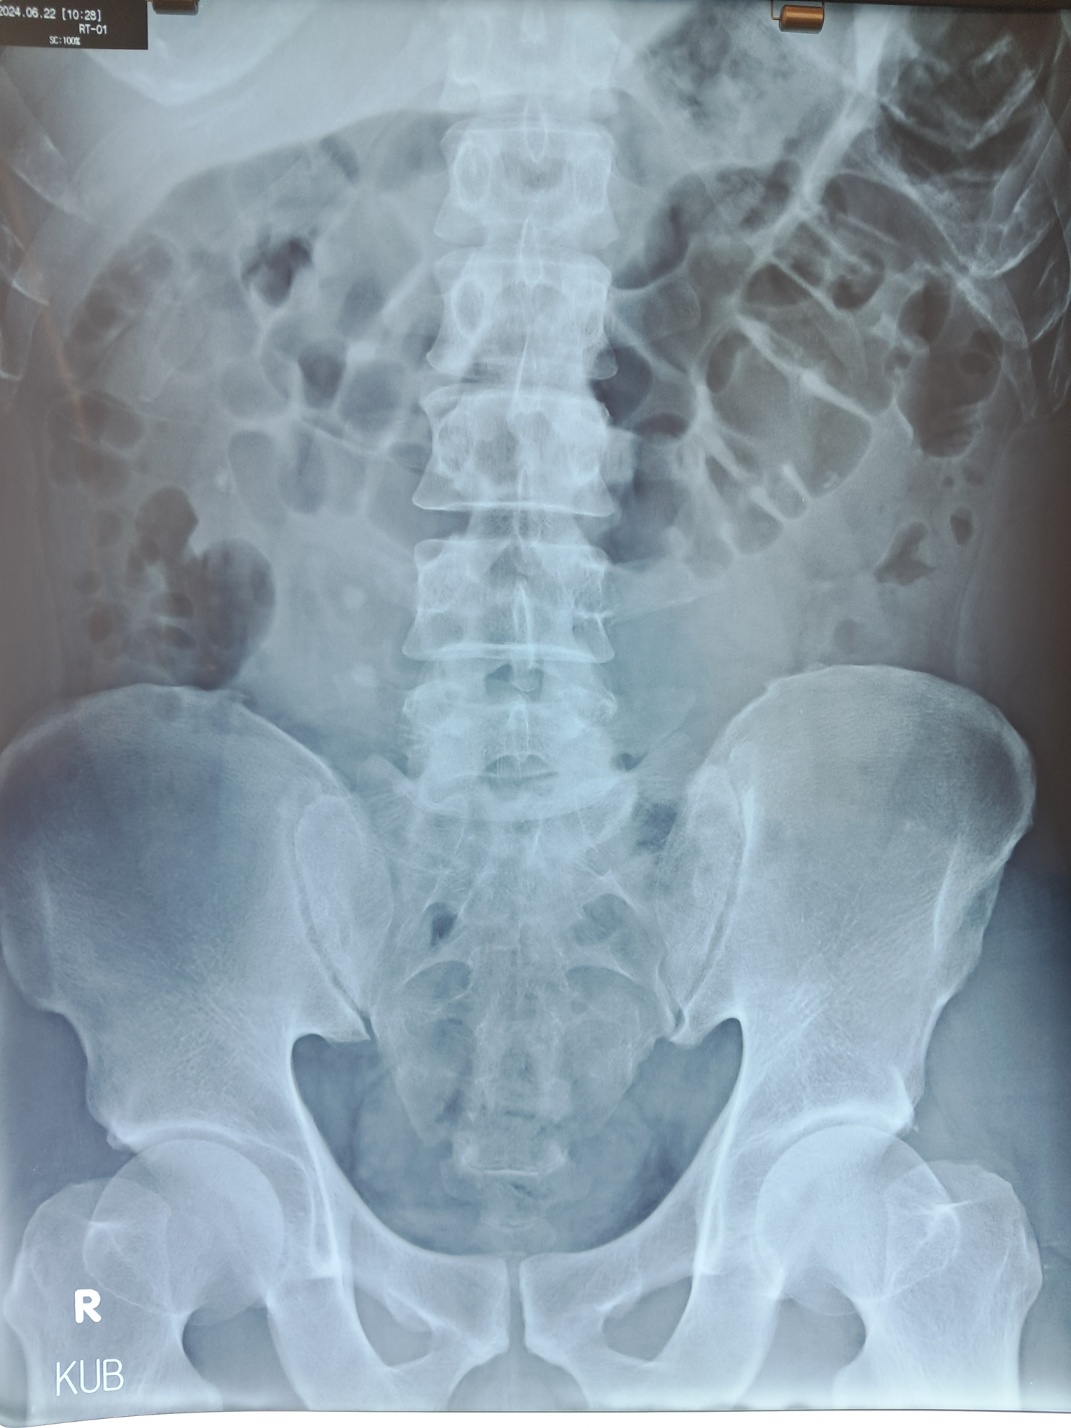

요로결석(尿路結石, Urolithiasis)은 신장, 요관, 방광, 요도 등에 돌(결석)이 생기는 질환입니다. 결석이 소변 배출을 방해하면 극심한 통증이 발생하며, 심한 경우 수술이 필요할 수도 있습니다.